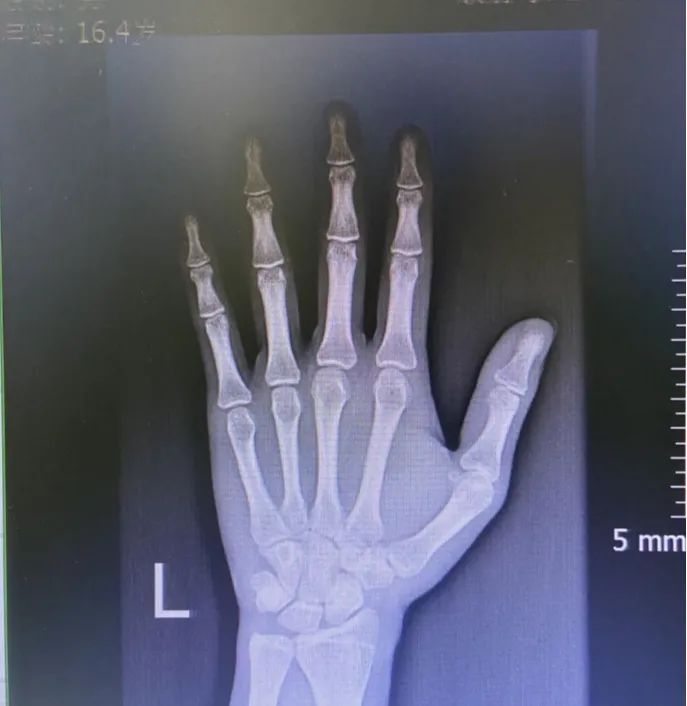

案 例 16岁的男孩小杨身高才156厘米,而且父母发现小杨今年身高没什么变化,好像已经停止生长了,赶紧带着他来看医生。 经过骨龄检查,结果显示小杨骨龄已经18岁了,比实际年龄早了2岁,再也没有长高的机会。即便注射生长激素进行干预,但根据骨龄预测小杨的成年终身高很有可能达不到1米6,因为他已经错过最佳的生长干预期。诊断结果让小杨父母追悔莫及。 ▲小杨的骨干骺端接近闭合 骨龄,决定着生长空间 骨龄就像车上的汽油,用一点少一点。 骨龄跑的慢,油耗低,跑得远跑的长; 骨龄跑得快,油耗高,跑得近跑得短。 我们看下还有生长空间的孩子生长板是什么样的: ▲左图为4.7岁孩子的生长板,清晰可见 右图为17岁男孩,骨干骺端完全闭合,生长板消失 ▲膝关节X光片 通过小杨的案例, 我们可以得到下面两个重要结论: 一、定期监测骨龄,评估生长发育情况 为什么医生总是提醒家长,孩子应该从3岁开始定期监测骨龄? 定期监测骨龄,能够及时地评估孩子的生长发育情况,预测孩子还能长多高,成年终身高是多少,医生也可以因此制定相应的身高管理方案,帮助孩子达到理想身高。 骨龄检测(3-15岁), 预测成年终身高、判断发展潜力 售价258元, 点击下图即可了解详情~ 点击↓↓↓ 二、生长期要抓牢,身高管理要尽早 一个人身高的80%是在青春期之前完成的,越小进行身高管理,骨干骺端距离闭合的时间越长,干预的方法也越多。每早一年干预,孩子就可能多长1-2cm,越容易达到期望身高。 越晚进行身高管理,不仅干预的方法少,花费也更高,达到期望身高的难度也更大。 科学长高管理(3-14岁), 定制管理计划,特色管理方案, 仅需1280元/年! 点击下图即可了解详情~ 点击↓↓↓ 最后,提醒各位家长朋友,如果孩子的身高一直不理想或者想要孩子长到期望身高,就应该尽早地做身高检查,评估生长发育情况,尽早干预,做好身高管理,定期监测骨龄。